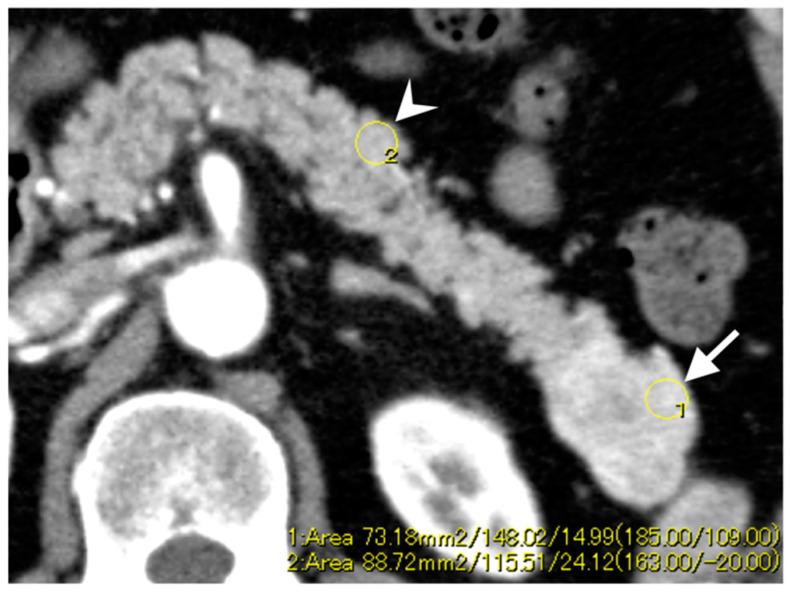

Paired box 6 (PAX6) is a transcription factor that plays a critical role in tumor suppression, implying that the downregulation of PAX6 promotes tumor growth and invasiveness. This study aimed to examine dynamic computed tomography (CT) features for predicting pancreatic neuroendocrine neoplasms (Pan-NENs) with low PAX6 expression. We retrospectively evaluated 51 patients with Pan-NENs without synchronous liver metastasis to assess the pathological expression of PAX6. Two radiologists analyzed preoperative dynamic CT images to determine morphological features and enhancement patterns. We compared the CT findings between low and high PAX6 expression groups. Pathological analysis identified 11 and 40 patients with low and high PAX6 expression, respectively. Iso- or hypoenhancement types in the arterial and portal phases were significantly associated with low PAX6 expression ( = 0.009; = 0.001, respectively). Low PAX6 Pan-NENs showed a lower portal enhancement ratio than high PAX6 Pan-NENs ( = 0.044). The combination based on enhancement types (iso- or hypoenhancement during arterial and portal phases) and portal enhancement ratio (≤1.22) had 54.5% sensitivity, 92.5% specificity, and 84.3% accuracy in identifying low PAX6 Pan-NENs. Dynamic CT features, including iso- or hypoenhancement types in the arterial and portal phases and lower portal enhancement ratio may help predict Pan-NENs with low PAX6 expression.

配对盒基因6(PAX6)是一种转录因子,在肿瘤抑制中起关键作用,这意味着PAX6的下调会促进肿瘤生长和侵袭性。本研究旨在探讨动态计算机断层扫描(CT)特征对预测低PAX6表达的胰腺神经内分泌肿瘤(Pan-NENs)的价值。我们回顾性评估了51例无同步肝转移的Pan-NENs患者,以评估PAX6的病理表达。两名放射科医生分析术前动态CT图像以确定形态学特征和强化模式。我们比较了低PAX6表达组和高PAX6表达组的CT表现。病理分析分别确定了11例低PAX6表达患者和40例高PAX6表达患者。动脉期和门脉期等密度或低密度强化类型与低PAX6表达显著相关(分别为P = 0.009;P = 0.001)。低PAX6的Pan-NENs的门脉强化率低于高PAX6的Pan-NENs(P = 0.044)。基于强化类型(动脉期和门脉期等密度或低密度强化)和门脉强化率(≤1.22)的联合诊断在识别低PAX6的Pan-NENs时,敏感性为54.5%,特异性为92.5%,准确性为84.3%。动态CT特征,包括动脉期和门脉期等密度或低密度强化类型以及较低的门脉强化率,可能有助于预测低PAX6表达的Pan-NENs。